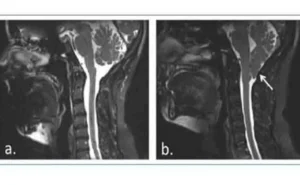

Si tratta di una malformazione dovuta a uno sviluppo incompleto della parte posteroinferiore della base del cranio durante il periodo embrionale, che può accompagnarsi a complicazioni quali siringomielia e idrocefalia.

La forma più estrema consiste nell’erniazione delle strutture della porzione più bassa del cervelletto, le tonsille cerebellari, e del tronco encefalico attraverso il forame magno, in modo tale che alcune parti del cervello raggiungono il canale spinale ispessendolo e comprimendolo.

La Malformazione di Chiari di tipo I comporta una erniazione caudale delle tonsille cerebellari di circa 5 mm al di sotto del forame magno, che di solito non si accompagna a discesa del tronco encefalico o del quarto ventricolo né a idrocefalia, ma a siringomielia.

La siringomielia è causata dalla formazione di cavità o cisti (siringe o syrinx) piene di liquido all’interno del midollo spinale, che possono espandersi lentamente, provocando un danno progressivo al midollo spinale e ipertensione intracranica dovuta alla pressione esercitata da tale liquido.